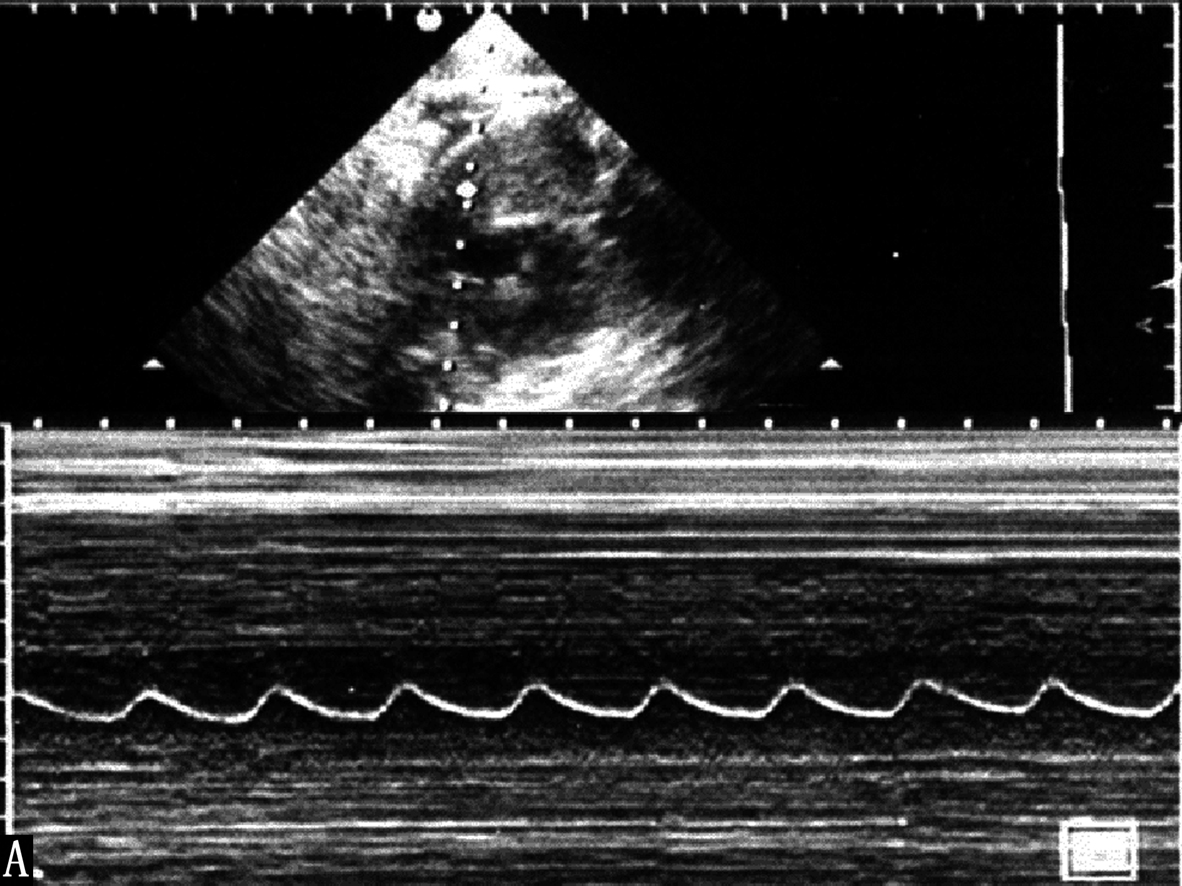

图2-A正常胎心显示规律的瓣膜活动曲线